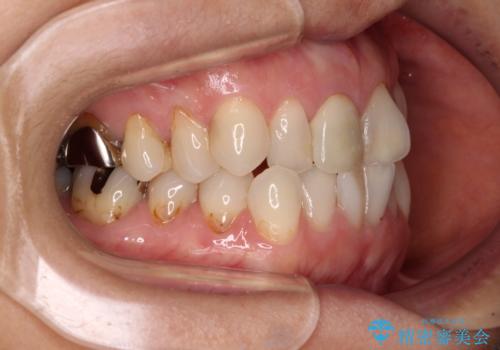

デコボコと銀歯 矯正治療とセラミック治療で綺麗な口元に

- 前歯のデコボコと口を開けたときに見える銀歯を気にして来院された患者様です。

ある程度デコボコが解消されれば大丈夫とのことで、インビザライン・モデレートパッケージを利用して歯列を整えて行くこととしました。

矯正治療後に銀歯をセラミッククラウンなどに置き換えていくと、どうしても後戻りを起こしてしまうため、矯正治療が概ね終了した時点で銀歯を全てセラミックとし、最後に仕上げでインビザラインにを用いて細かいデコボコを改善していくこととしました。